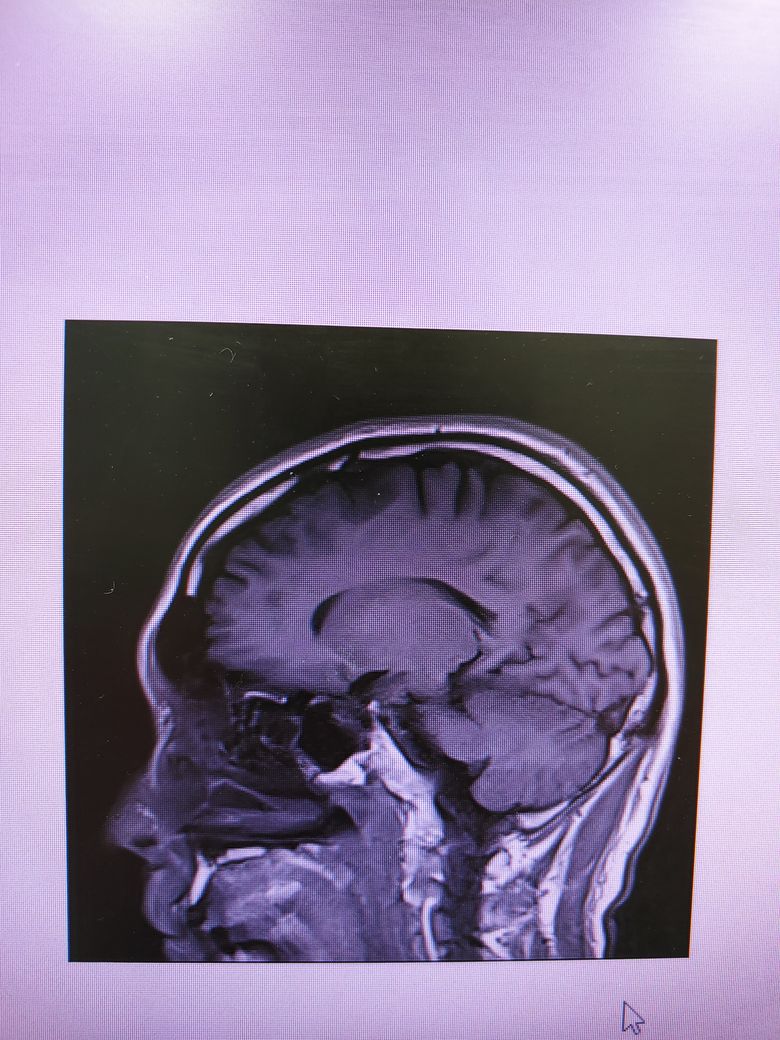

• 3번 째 사진

4컷만으로는 MRI에 대한 충분한 판독이 어렵지만 큰 이상은 없는것으로 보입니다.

특이 이상소견은 보이지 않으나 mri의 경우 4장으로 판단하는 것이 아닌 각 단면마다의 연속적인 영상을 보아야 알수 있습니다. 그리고 각 setting마다 볼수 있는 것도 다르며 보다 명확한 평가를 위해서 담당 선생님께 보다 구체적인 설명을 들으시길 바라며 최근 멍한 증상이 심해졌다면 뇌파 검사 등이 요구될수 있습니다. 우선적으로 기존에 다니셨던 병원을 내원해 진료를 보시고 추가적으로 신경과 내원 또한 고려해볼 수 있습니다. 감사합니다.

올려주신 사진 상에서는 이상소견이 확인되지 않습니다.

MRI의 경우 이렇게 몇컷만 보는것이 아니고 전체를 확인해야하기 때문에 다른 신경과 전문의 진료를 받아보시고 MRI 판독을 요청해보시는게 좋겠습니다.

이미 한번 괜찮다고 들으셨다고 하면 너무 걱정하실 필요는 없습니다. 그리고 MRI사진의 경우 1장만 가지고서 뇌 전체의 이상 여부를 확인할 수는 없답니다. 올리신 사진은 특별한 문제가 없지만 다른 사진에서 이상이 있을 수도 있거든요. 다시 한번 확인을 원하신다면 CD를 가지고 다른 병원에서 추가적인 의견을 들어보셔도 됩니다.